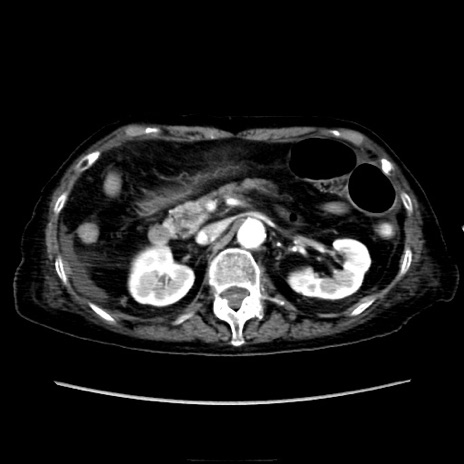

症例40(横断像)

【症例】90歳代女性

【主訴】腹痛・嘔吐

【現病歴】 食欲低下、嘔吐があり昨日他院受診。肺炎と診断され入院となる。入院後より腹部全体に圧痛あり。胃管留置され経過みていたが、症状持続するため、

当院転院となる。

【既往歴】胸椎圧迫骨折、胆石症

【身体所見】腹部:中央に激痛あり、圧痛あり、反跳痛不明

【データ】WBC 17100、CRP 18.82

横断像